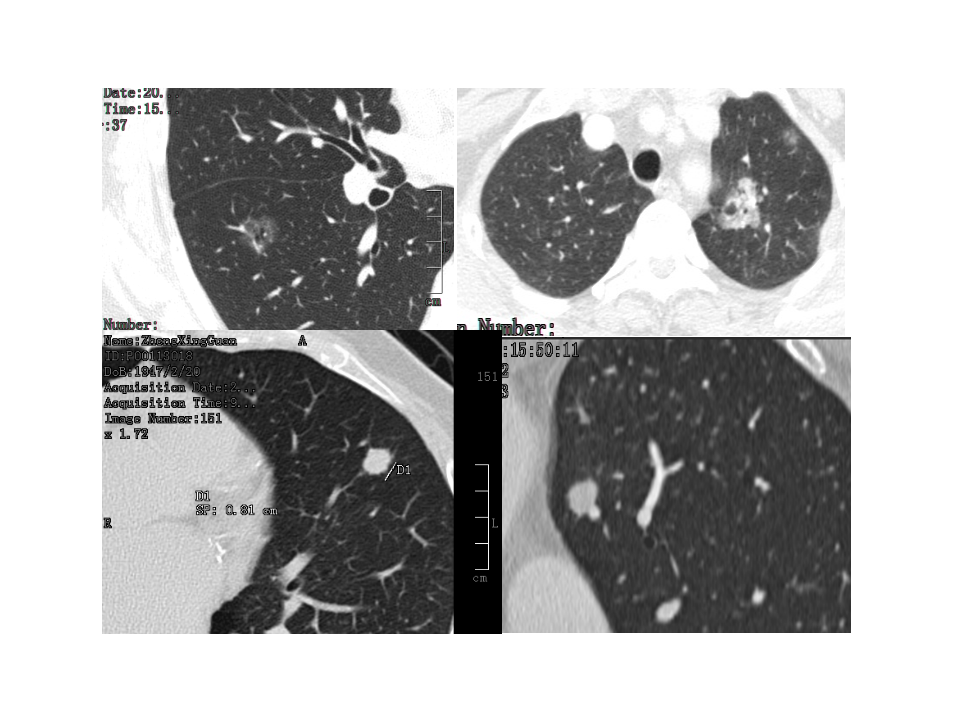

肺结节的应对策略.pptx

磨玻璃结节的影像分析--郭亮.pdf

伴囊性空腔肺癌的诊断与鉴别--邢伟.pdf